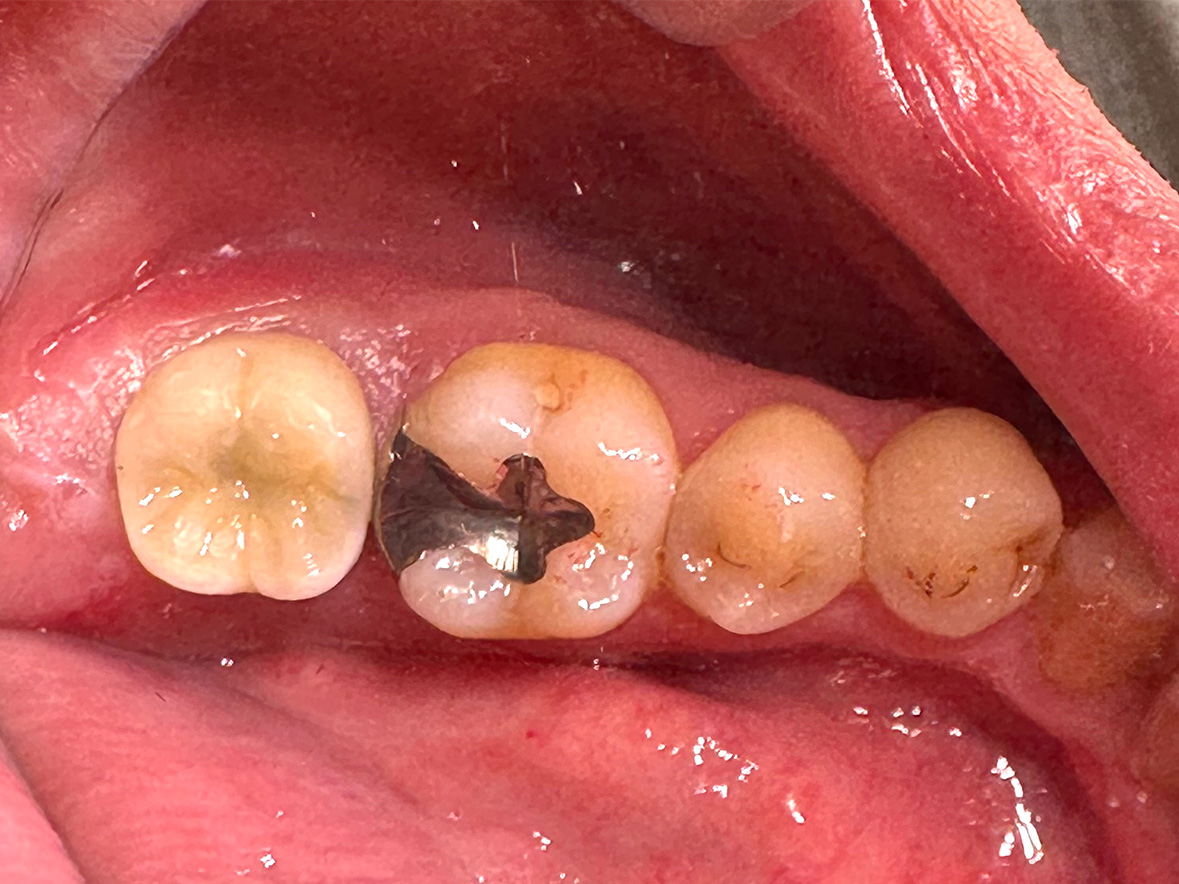

症例3

患者様の年齢 60代男性 主訴 歯が痛い 治療内容 左下456インプラント治療

抜歯即時インプラント埋入後3ヶ月の待機期間後、ジルコニアによる上部構造装着費用 77万円 治療期間・通院回数 4ヶ月/5回 デメリット・リスク 外科処置に伴う痛み・腫れ・出血・合併症の可能性があります。 -